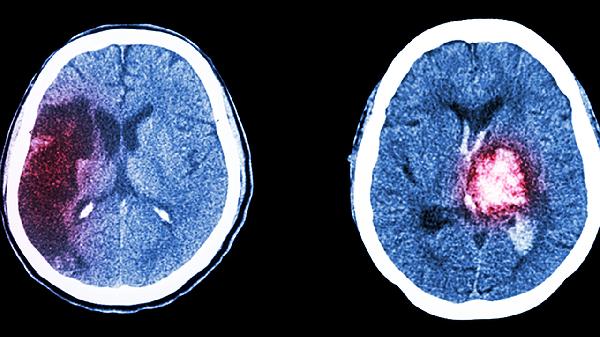

部分患者可能表现为不典型症状,如仅有口腔溃疡和皮肤病变,或仅有眼炎和生殖器溃疡。这类患者需长期随访以明确诊断。特殊情况下,如出现中枢神经系统或胃肠道受累,需进一步进行脑脊液检查、内镜检查或影像学评估。对于儿童或青少年患者,诊断时还需排除其他类似疾病,如克罗恩病或系统性红斑狼疮。